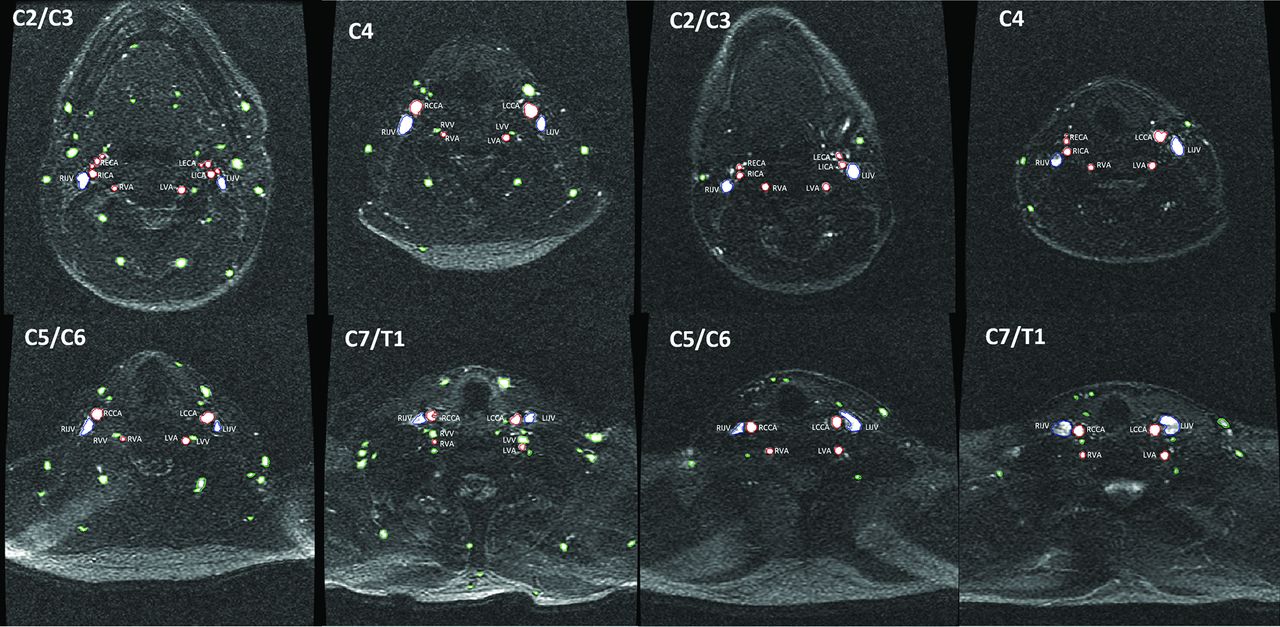

After we controlled for these confounding factors, patients with MS had a significantly lower CSA of the carotid arteries at C2/3 (55.1 ± 16.4 versus 60.9 ± 17.9, P = .03), C5/6 (50.1 ± 10.1 versus 53.9 ± 12.5, P = .026), and C7/T1 (47.6 ± 9.8 versus 52 ± 9.9, P = .005) levels, as well as of the vertebral arteries at the C2/3 (20.1 ± 4.4 versus 21.8 ± 5.8, P = .02), C4 (18.6 ± 4.2 versus 20.3 ± 5, P = .012), and C7/T1 (16.3 ± 4.5 versus 18.4 ± 5.9, P = .006) levels, compared with HC. A higher frequency of secondary neck vessels was found at all 4 levels in patients with MS: C2/3 (12.9 versus 10, P < .001), C4 (9.1 versus 7.5, P < .001), C5/6 (7.8 versus 6.8, P = .012), and C7/T1 (8.8 versus 6, P < .001). The total CSA of secondary vessels was also significantly higher at all 4 levels in patients with MS (P < .03). The difference was most significant at the C7/T1 level where the CSA of patients with MS was 71.1 ± 40.5 mm2 compared with 56.7 ± 32.5 mm2 in HC (P < .001). No significant differences in the CSA of the IJVs were found between MS and HC cohorts. Figure 2 shows an example of the differences in vessel number and CSA observed in patients with MS and age- and sex-matched HC.

Comparison of main and secondary vessel number and cross-sectional area on a 2D-MRV sequence at 4 cervical levels in patients with multiple sclerosis (4 corresponding panels on the left) and age- and sex-matched healthy controls (4 corresponding panels on the right). VV indicates vertebral vein; L, left; R, right. Green color represents the secondary vessels, red color represents the CCA, ICA, EAC, and VA, while blue represents the IJV.